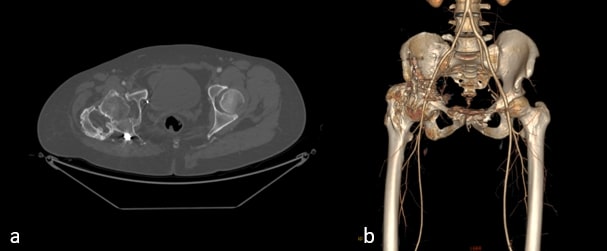

Radiographs demonstrated malunited anterior and posterior columns with retained implants, medial acetabular migration, and massive mature HO bridging the acetabulum and proximal femur (Brooker grade IV)(Fig 1). CT scan showed mal united fracture of both columns, heterotopic mass extending superior, anterior and posterior to the right proximal femur causing extra articular ankylosis(Fig 2 a). There also was intra articular ankylosis with trabeculae crossing the hip joint posteriorly fusing with the acetabulum. There was severe protrusio with intact medial wall. CT angiography superimposed images revealed the external iliac vessels closely abutting but not encased by the HO(Fig 2 b).